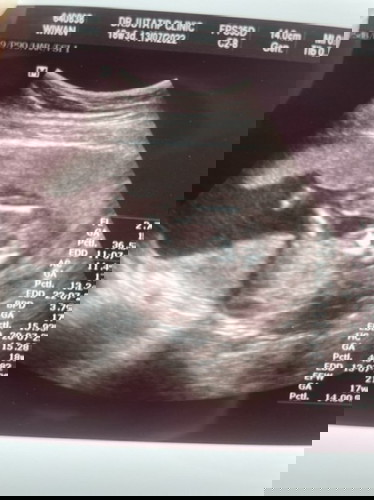

แม่ๆคิดว่าน้องเป็นเพศไหนคะ คุณหมอบอก ผู้หญิง 90% พอดีน้องไม่ค่อยอ้าขาค่ะ #ท้องแรกคะ